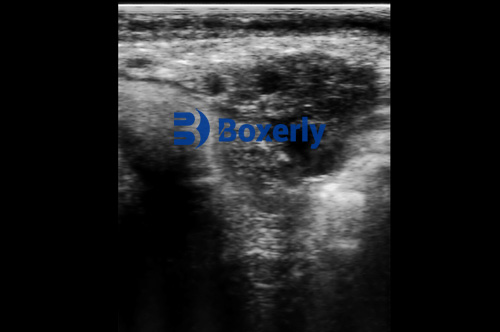

Handheld ultrasound devices allow producers to “see inside the animal—safely, instantly, and with remarkable accuracy”. By scanning organs, fat deposits, and muscles on the spot, users can make informed decisions about breeding, nutrition, or treatment without waiting for lab tests or shipping animals to clinics. This capability has led to a data-driven approach in animal agriculture: instead of guesswork, farmers get immediate visual feedback. For example, modern livestock ultrasound scanners are designed to be rugged and waterproof for field use. They produce high-definition, real-time images (often B-mode cross-sections) that veterinarians and trained farmers can interpret on location. In effect, handheld ultrasound democratizes diagnostic imaging, providing real-time insights that improve animal welfare and farm profitability.

Disease Screening: On-site ultrasound can detect internal health issues before they become clinical. In young cattle, for example, scanning the chest can reveal pneumonia lesions that would otherwise be hidden. Abdominal scans can identify gut obstructions, abscesses, or liver abnormalities without surgery. In horses (often included under farm animal care), ultrasound is also routinely used to diagnose tendon injuries or colic (intestinal obstruction) quickly.